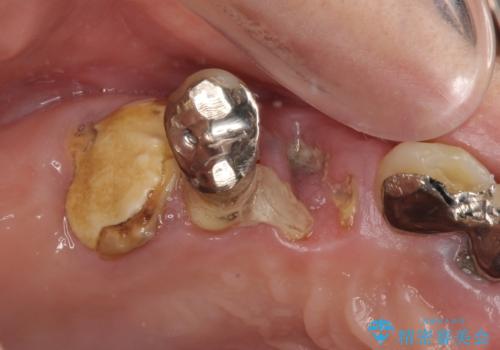

- 歯が破折しているため、抜歯が必要であると近医で診断されてからも放置を続けてしまったとのことで来院された患者様です。

臼歯はもはや咬み合わせに寄与していない状態であり、3歯を抜去してインプラント2本埋入によるブリッジ補綴を計画しました。

臼歯部は前歯以上に炎症が酷く、抜歯即時埋入不可と判断されましたが、従来法よりは短期間で終えることができました。